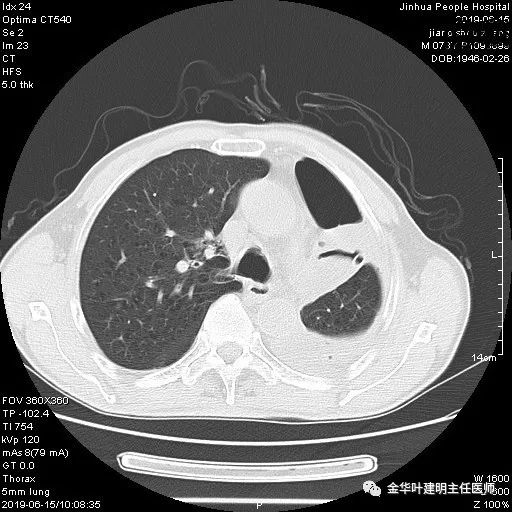

考虑左侧大量胸腔积液,遂进一步胸部CT检查:

以上是肺窗表现,下面为纵隔窗影像: